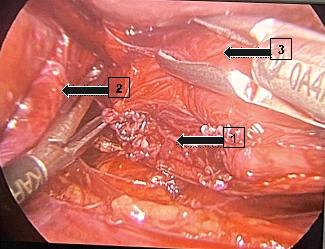

Once the patient's case had been discussed, with an indication for surgical treatment, the procedure was carried out using laparoscopy, which is usually used to approach the Esophagogastric transition, to correct the patient's diverticulum, without any complications 3 months after the case was first investigated, at the São Marcos Hospital in Uberaba, Minas Gerais, with a satisfactory result and a significant improvement in obstructive sleep apnea and gastrointestinal symptoms. The procedure involves making small incisions in the abdominal wall, through which surgical instruments and the laparoscope are inserted. The surgeon uses the laparoscope to visualize the area to be operated on, and after dissecting the diverticulum, it is resected using a linear endo grammar. The year after the procedure, the patient returned for a follow-up visit, reporting a significant improvement in her previous symptoms. She only complained of persistent heartburn in the epigastric region, which led to a request for a new upper gastrointestinal video endoscopy (Figure 3), which again showed a negative result for H. Pylori (using the urease test), a linear scar at 35cm from the incisors, and a persistence of erosive antral gastritis, identified in the previous year's examination, before the surgical procedure, which led to the conclusion that the erosive antral gastritis was not related to the presence of the diverticulum. As a result, clinical treatment with a proton pump inhibitor was prescribed, with a satisfactory result in the patient's clinical improvement (Figure 4, Figure 5).

Figure 4 Intraoperative photograph of the laparoscopy. Arrow (1) liver, Arrow (2) epiphrenic diverticulum.

Figure 5 Intraoperative photograph after resection of the diverticulum. Arrow (1) Stapling area of the diverticulum resection, Arrow (2) Diaphragmatic pillar, Arrow (3) Esophagus.